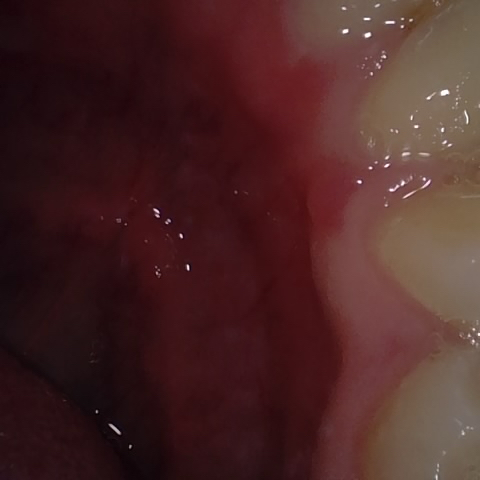

NHD20794

Annotated as "Good"